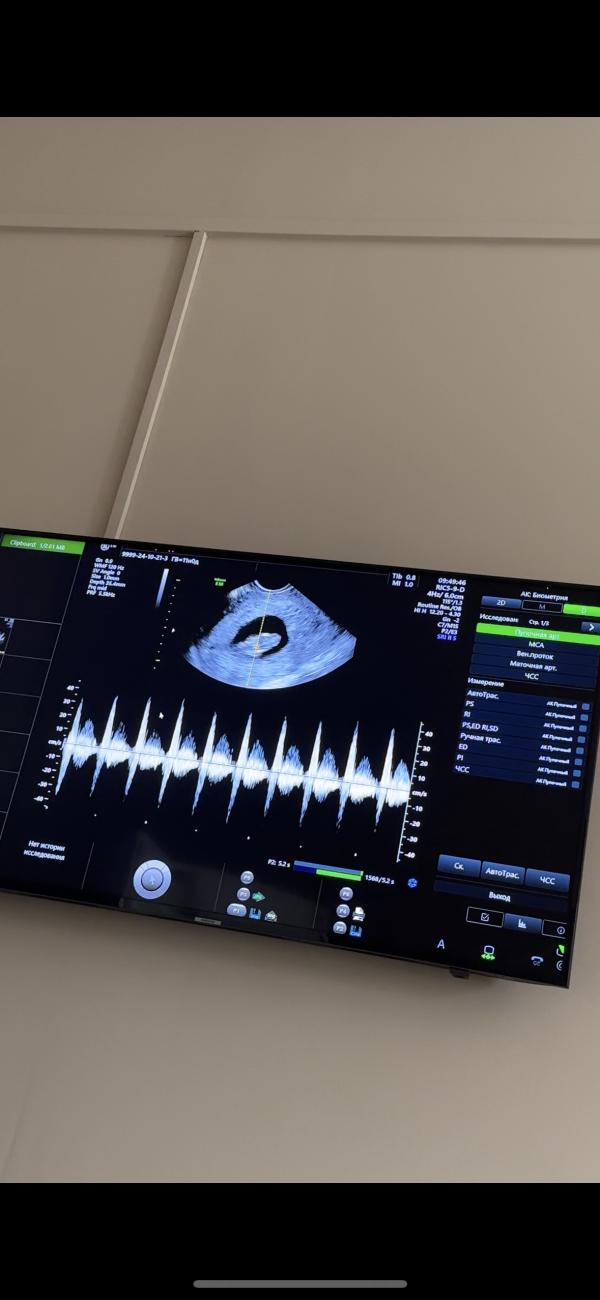

Когда услышала впервые сердцебиение Малыша, это нереальные эмоции. Плакала от счастья 😍😍😍

В начале сказали что ничего не видно, нет сердцебиение , я испугалась накручивала себе разные мысли. У Вас тоже так было? 😀🙈

Блин мне тоже так сказали, я в такую панику впала. Потом внутривагинально посмотрели и мы услышали сердечко 🥹я начала тихо плакать